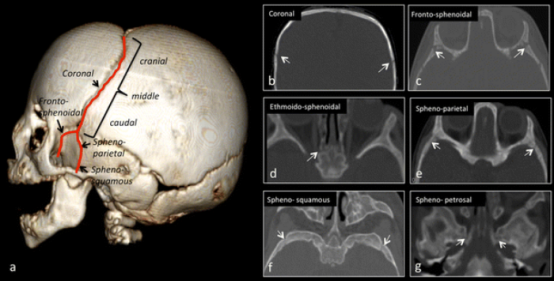

图2:冠状弓(a)起始于前囟;由冠状缝(白色箭头,b)组成,每个冠状缝分为前支和后支。前支由额蝶缝(白色箭头,c)和筛蝶软骨联合(白色箭头,d)构成;后支由蝶顶缝(白色箭头,e)、蝶颞缝(白色箭头,f)和蝶岩软骨联合(白色箭头,g)构成。

图 3:面颅缝。3D-CT(a)和2D-CT(b–h)。低剂量 CT 扫描中可见的面颅缝(a)。额颧缝(白色箭头:开放缝,b)额上颌缝(白色箭头:开放缝,c)鼻缝(白色箭头:开放缝,d)额鼻缝(白色箭头:开放缝,d)鼻上颌缝(白色箭头:开放缝,e)颞颧缝(白色箭头:开放缝,f)蝶颧缝(白色箭头:开放缝,g)颧上颌缝(白色箭头:开放缝,h)眶额缝在低剂量 CT 扫描中不可见。